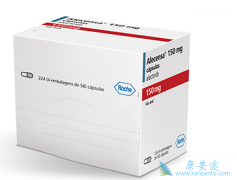

前年,欧盟委员会(EC)批准 乐伐替尼 (Lenvatinib、仑伐替尼、Lenvima)作为一种单药疗法,用于晚期/不可切除性肝细胞癌(HCC)成人患者的一线治疗。乐伐替尼去年已在美国和日本获批相同适应症。这是乐伐替尼在获批治疗甲状腺癌和肾癌之后的最新适应 ...